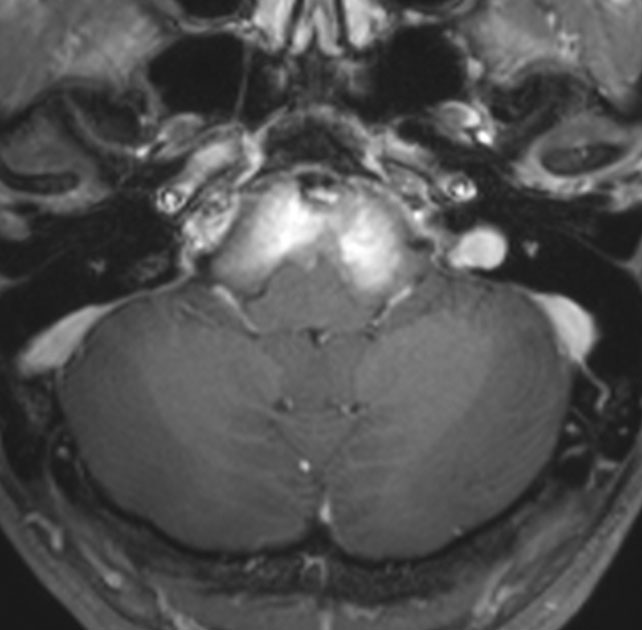

典型的な神経腸嚢胞 neurenteric cyst

左のT2強調画像で等信号,中のT2*で高信号,右はCISS画像です。

T1強調画像では,のう胞周囲の高信号の部分は半固体で,中心部の高信号はドロドロの粘液でした。基本的にガドリニウム増強はされません。まれに薄い膜状に一部が増強されることがあります。

境界明瞭は袋状の腫瘍です。椎骨動脈や脳底動脈を包み込むようにふくらんでいます。

左外側後頭下開頭という小さな開頭手術だけで全摘出しました。術後は幸い何の症状も出ていません。この例は脳幹部に食い込まないもので,運良く全摘できたのですが,そうはいかないものもあります。